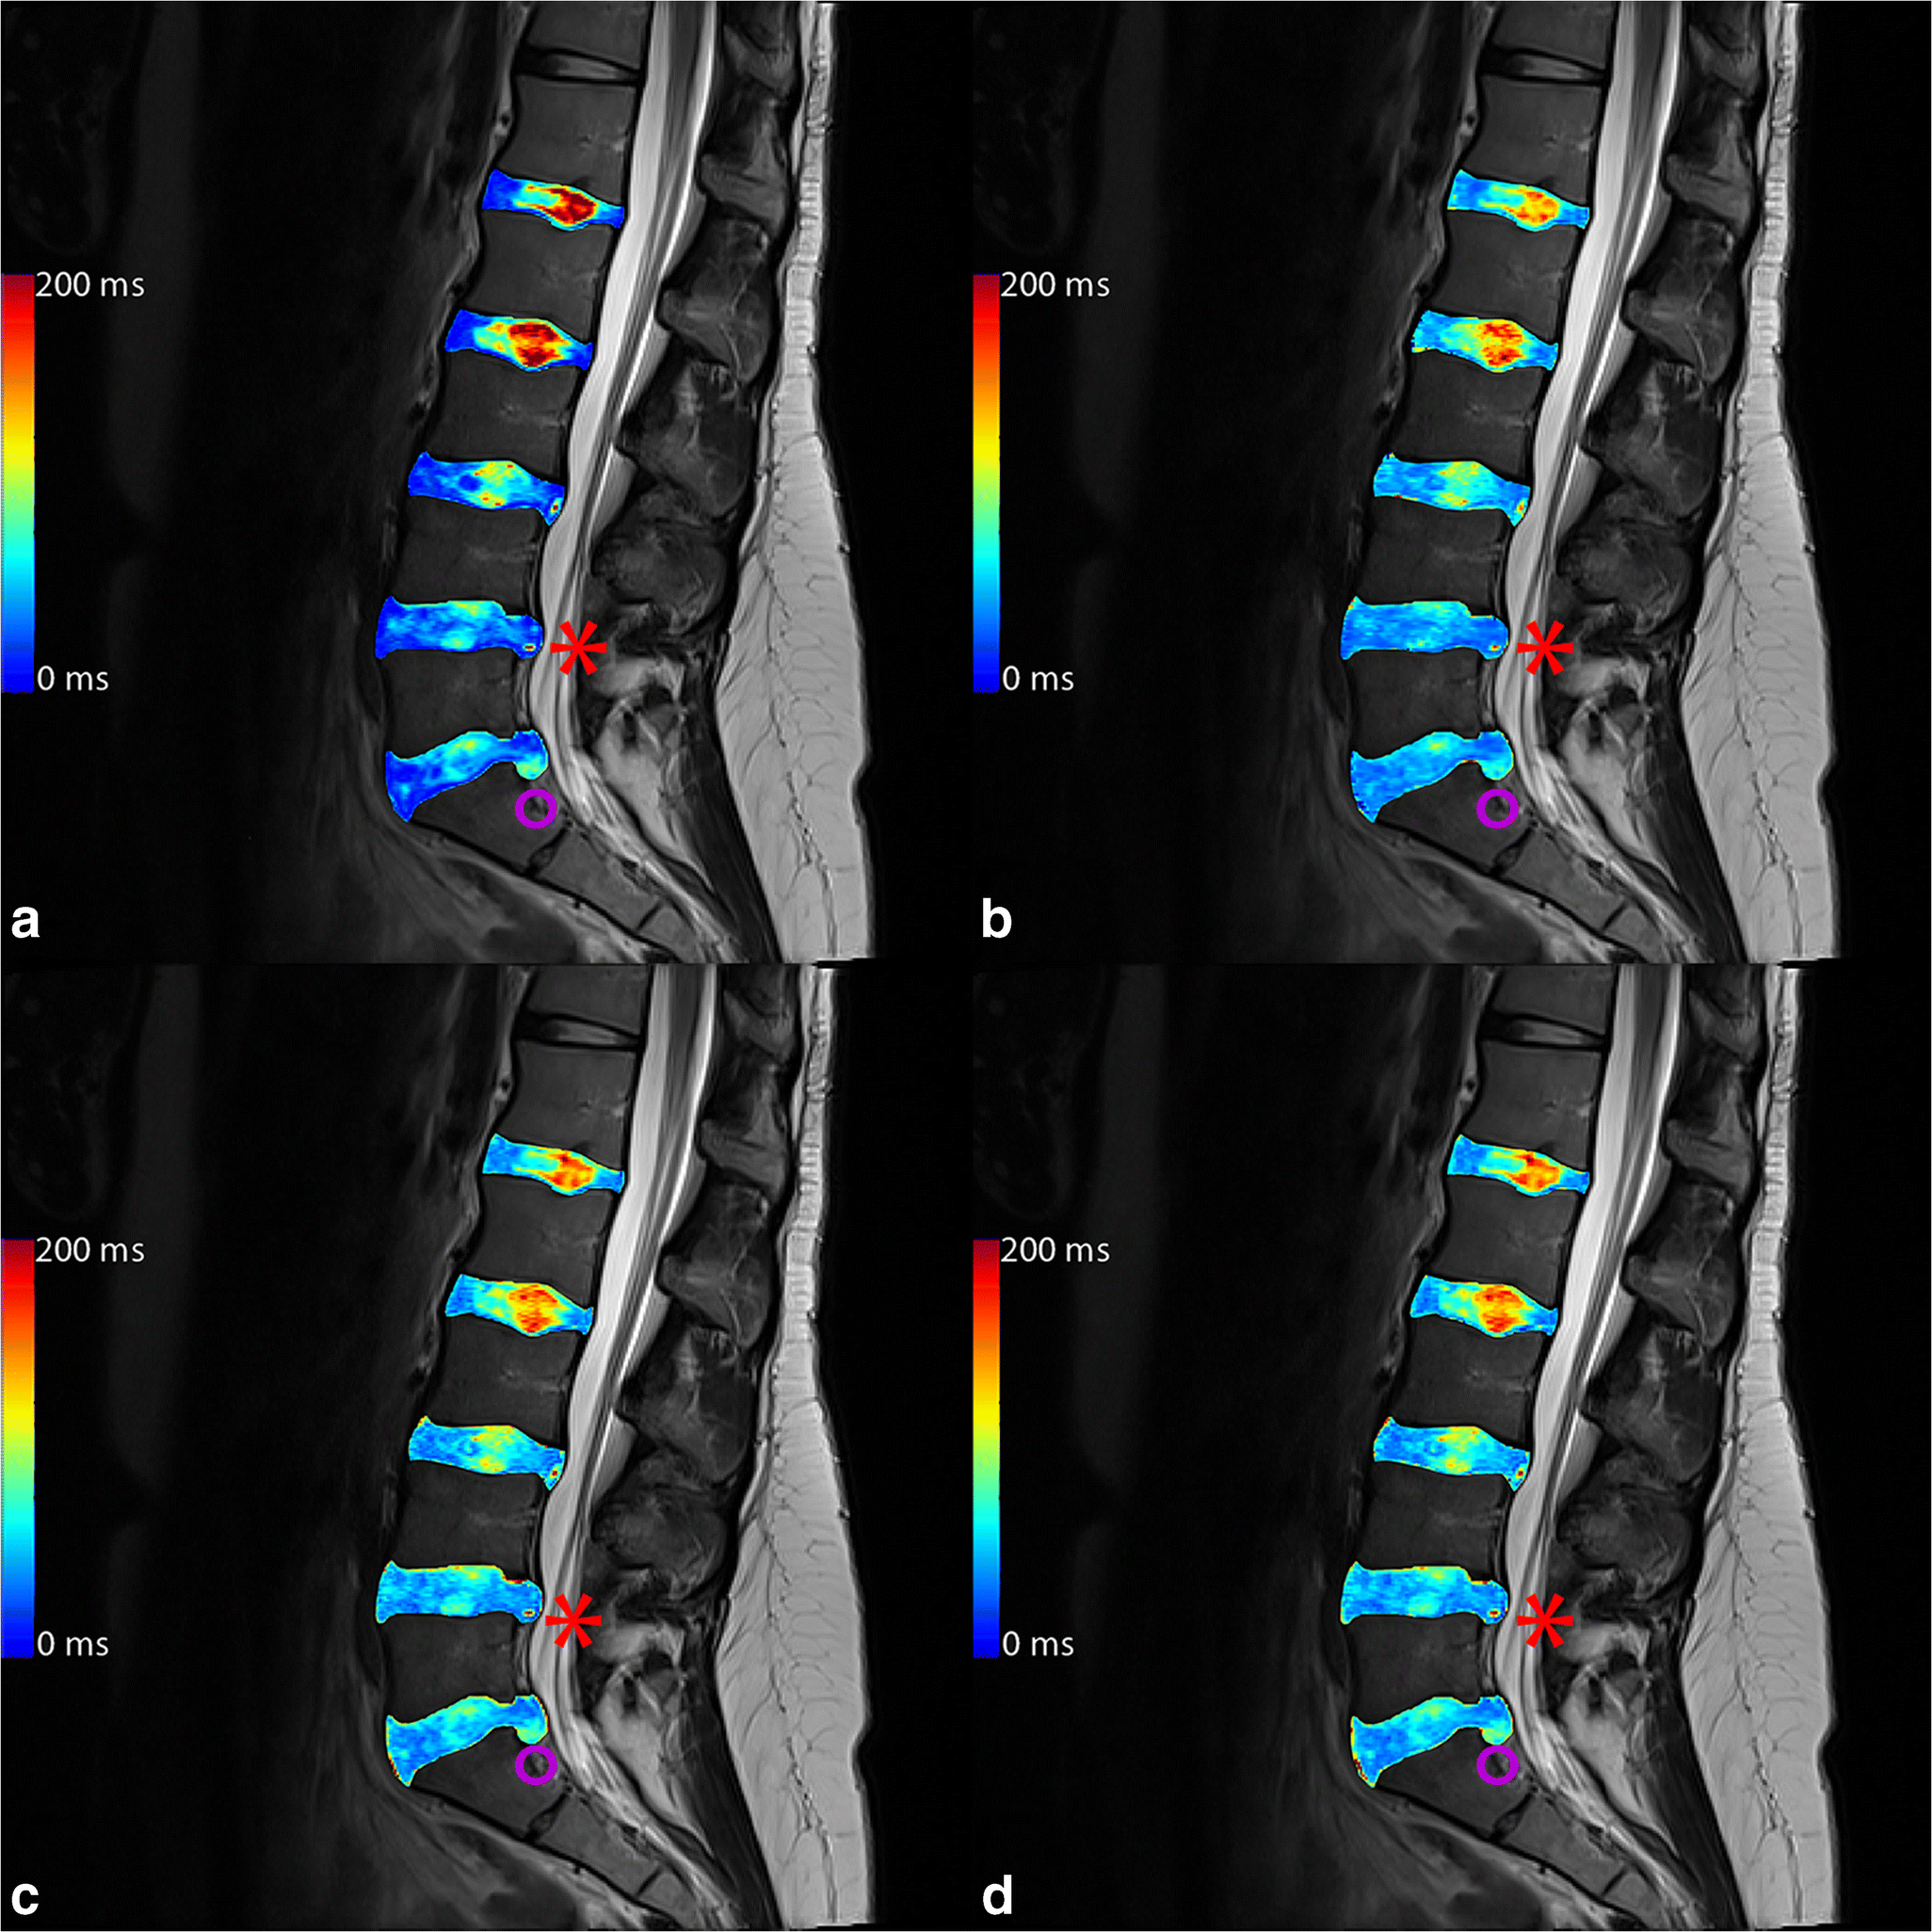

For the posterior annular region, only T2-GRAPPATINI showed a significant difference (p = 0.011) between normal and herniated discs. All other group comparisons of T2-GRAPPATINI, T2-MESE, T2-EVEN, and T2-WO1ST showed non-significant results (p = 0.086 to 0.999). An example of a patient with herniation in segment L5/S1 is given in Fig. 2 with color-coded T2 map overlays.

Fig. 2

Color-coded T2 map overlays of (a) multi-echo spin-echo (MESE), (b) GRAPPATINI, (c) EVEN, and (d) WO1ST. The purple circle marks a herniating L5/S1 disc with annular tear with nucleus pulposus tissue in the lower posterior annular region of interest, resulting in higher, pathological T2 at that very place and a consecutive acute bone marrow edema in L5